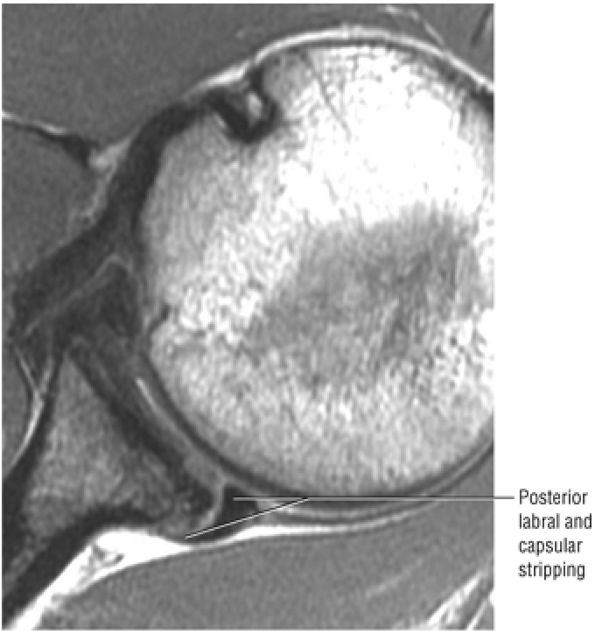

FIGURE 8.102 ● (A) The anterior undersurface of the acromion and the coracoacromial ligament form the coracoacromial arch. The subacromial subdeltoid bursa facilitates the passage of the rotator cuff and proximal humerus under the coracoacromial arch. (B) A superior axial image shows the anterior-to-posterior extent of the coracoacromial (CA) ligament perpendicular to the supraspinatus tendon. The fluid in the subacromial-subdeltoid bursa represents fluid between two serosal surfaces in contact with each other. One serosal surface is contributed by the undersurface of the coracoacromial arch and deltoid, and the other serosal surface is on the bursal side of the cuff.

|

![]() |

FIGURE 8.103 ● Pseudospur. The normal broad attachment of the coracoacromial ligament to the inferior surface of the acromion is shown on (A) T1-weighted coronal oblique and (B) sagittal oblique images. The low-signal-intensity acromial cortex (black arrows) and adjacent coracoacromial ligament and lateral slip of the deltoid attachment (white arrows) give the false impression of a small subacromial spur in the coronal plane. This pseudospur should not be misinterpreted as impingement; otherwise, unnecessary acromioplasties may be performed on patients with a normal coracoacromial ligament attachment and no associated acromial spurs.

-

Impingement syndrome, a clinical diagnosis, is characterized by a range of MR findings from tendinosis to rotator cuff tears.

Intrinsic impingement is associated with shoulder instability.